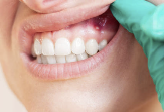

1. 치은염 – 가장 흔한 잇몸 붓기의 원인

- 구강 위생 불량으로 생긴 **치태(플라그)**가 잇몸에 쌓이며 염증 유발

- 잇몸이 선홍색이 아니라 붉거나 자줏빛으로 변하며, 쉽게 붓고 피가 남

- 칫솔질만 해도 잇몸이 아프고 시큰해짐